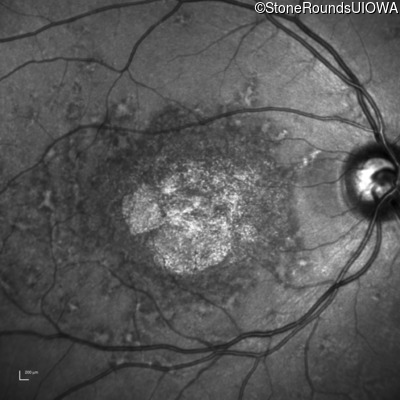

AR Stargardt Disease (IIA)

Age at visit: 35 years

This 35 year old woman first started holding her reading material closer than normal when she was 7 years old.

Diagnosis & molecular findings

AR Stargardt Disease ABCA4 Val1681 del15gctGTGGTTGCCATCTGC Gly1961Glu GGA>GAA AR